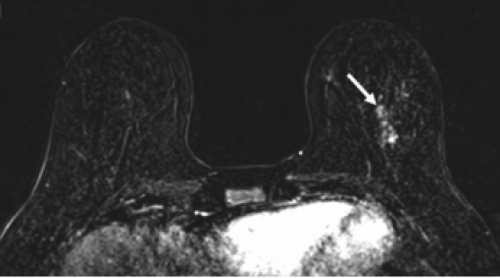

18 tháng 08, 2025Chụp MRI có thể phát hiện ung thư vú Nghiên cứu mới chứng minh chụp MRI phát hiện ung thư vú sớm hơn nhũ ảnh và siêu âm, đặc biệt hiệu quả ở phụ nữ có nguy cơ cao. Xem thêm